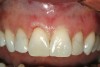

Figure 10  Facial view of the gingival tissues 9 weeks after open-flap surgery and at the time of placement of the ceramic restorations (original magnification 2x). Note the symmetrical positioning of the gingival zeniths of tooth Nos. 8 and 9. The level of tissue health 9 weeks after surgery is excellent.

Figure 10